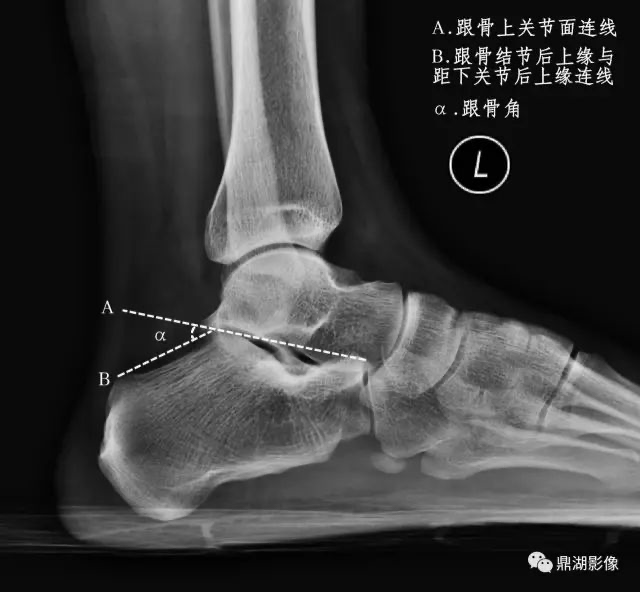

跟骨角

-

正常值:男性28°~40°,女性25°~42°

距跟后关节上缘和跟骨结节后上缘的连线与跟骨上关节面连线间的夹角

跟骨角变小,提示有扁平足或跟骨骨折;角度增大,提示弓形足